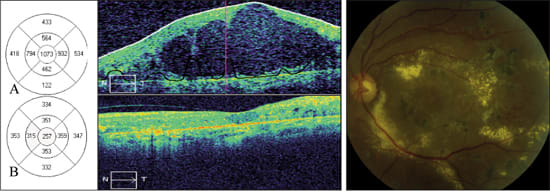

Figure 1. Sequential SD-OCT images from a 60-year-old male with diabetic macular edema in the right eye. Color fundus photograph shows diabetic retinopathy with macular edema.

A: Horizontal scans through the fovea show loss of the normal foveal contour, diffuse macular thickening, and intraretinal cysts. The retinal map shows a central foveal thickness of 541 μm. Best-corrected visual acuity was 20/60+3.

B: Two months after grid laser photocoagulation, SD-OCT reveals marked improvement of foveal thickness (281 μm) and contour. Best-corrected visual acuity improved to 20/40.

A 60-year-old male with an 18-year history of non-insulin dependent diabetes presented with bilateral decreased vision. His other medical problems included hypertension and dyslipidemia. On initial examination, he was noted to have prior extensive panretinal photocoagulation in the left eye and diffuse macular edema in both eyes. Best corrected visual acuity (BCVA) in the right eye was 20/60+3. SD-OCT revealed cystoid macular edema (CME) with a central foveal thickness of 541 microns (Figure 1A).

The patient was treated with a single intravitreal bevacizumab (1.25 mg/0.05ml) injection in the right eye. At one month follow up, there was no improvement in BCVA or SD-OCT from baseline. The patient was subsequently treated with grid laser photocoagulation directed at the areas of leakage as demonstrated by fluorescein angiography. At two months, best corrected visual acuity was 20/40. SD-OCT showed improved macular edema and a central foveal thickness of 281 microns (Figure 1B). By six months, visual acuity improved to 20/30 and SD-OCT measurements continued to improve despite no further laser treatment.